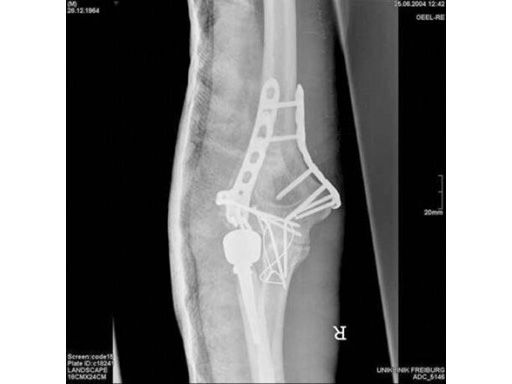

85-year-old woman, 13-C3, low supracondylar fracture treated with DHP.